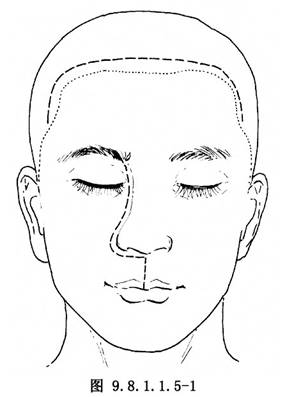

(2)切口:切口線設計要注意兩點:①由於下方尚有頜面部手術,面動脈及眶上動脈均可能無法保留,因此,額顳部冠狀切口下端應設在顳動脈後方。②前顱底缺損區可能需用頭部腱膜瓣修復,故應具體測量所需長度(即由眶上緣到骨窗下緣高度乘以2,再加前顱底缺損區的距離,而且要讓此瓣後端伸到蝶骨平板後方,無張力,並稍有富餘)。其總長度,由眶上緣起,向後上約10cm。皮膚切口在髮際後1cm,但腱膜切開線應向後延到上述足夠長度。設計完成後於腱膜下注射腎上腺素鹽水,以利翻瓣操作。由於頭皮部血運豐富,切口宜分段切開。切開一段,控制出血後再延長另一段。兩側切口到耳上5cm;鼻側按上頜骨切除取切口(圖9.8.1.1.5-1)。